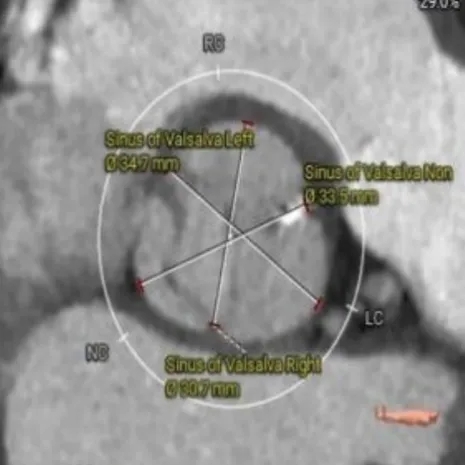

术前CT评估:功能性二叶瓣,左右融合嵴伴钙化,瓣叶增厚,瓣环径26.5,LVOT:28.7,瓣上可打开至23左右,窦部空间可,双侧冠脉开口高度可,主动脉弓大弯侧无明显钙化,双侧髂股动脉内径偏细,右侧股动脉分叉位于股骨头平面中部,左侧股动脉分叉位于股骨头平面中下1/3,建议右侧股动脉入路。

CT影像: